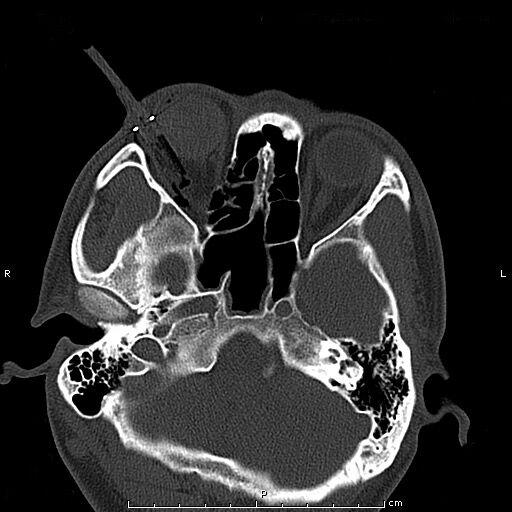

患者青年男性,因“右眼被鋼筆戳傷2小時余”入院,眼科查體:視力:右無光感,左0.4。眼壓:右不能檢查,左正常。右眼上瞼紅腫,鋼筆自顳上方眼瞼刺入,末端位置不詳,睜眼困難;結(jié)膜充血、水腫,角膜尚清,前房積血,余眼內(nèi)結(jié)構(gòu)窺不入。左眼未見明顯異常。入院后完善眼眶CT檢查,印象:右眼眶異物并右眼球破裂傷、眶內(nèi)壁骨折,異物嵌頓于眶壁。鋼筆內(nèi)含墨水,傷情重且復(fù)雜。